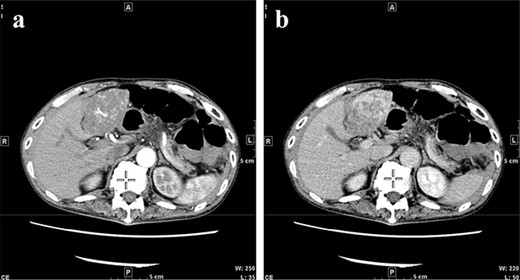

A 77-year-old man was referred to the Department of Gastroenterology at our hospital for suspicion of hepatocellular carcinoma and cancerous peritonitis. He was scheduled to be hospitalized for a thorough examination at a later date. However, 3 days after his first visit, he returned to the Emergency Department with a complaint of abdominal distension. He was hospitalized on the same day with a diagnosis of intra-abdominal bleeding due to a ruptured tumor in the lateral section of the liver. Computed tomography (CT) and magnetic resonance imaging (MRI) revealed a tumor with a maximum diameter of 8 cm in the lateral hepatic region and ascites around the liver and in the pelvic floor. Dynamic CT showed blood vessel-like early staining inside the tumor, and the contrast effect gradually enhanced (Fig. 1). During gadolinium ethoxybenzyl diethylenetriamine pentaacetic acid-enhanced MRI, this contrast effect gradually increased from the peripheral part toward the hepatocyte phase from the arterial phase (Fig. 2). Levels of tumor markers (alpha-fetoprotein, protein induced by vitamin K absence or antagonist-II, carcinoembryonic antigen and carbohydrate antigen 19–9) were within the normal range (Table 1). Based on the imaging findings, a diagnosis of spontaneously ruptured hepatic hemangioma was made. Since the patient’s general condition was stable and there were no findings suggestive of active bleeding, he decided to undergo elective surgery. Thus, he was not requested to continue being hospitalized and was discharged. Six days after discharge, he was transported to the emergency room in a state of shock and was hospitalized the same day. With the diagnosis of hemorrhagic shock due to re-rupture of the liver tumor (Fig. 3), emergency transarterial embolization (TAE) was performed. No apparent extravasation was observed on angiography, and A3 was embolized. Seven days later, he underwent left lateral hepatic segmentectomy. The postoperative course was generally good. The post-ruptured tumor was found in the left lateral segment, the cut surface was white, the edges were brown and the boundaries were unclear (Fig. 4). Histopathological examination revealed that sections of the white and brown parts of the margin were viable tumors, showing highly atypical spindle-shaped cells, arranged like sinusoidal vessels and partly solid, and there were many mitotic figures. There was no capsule, and the tumor infiltrated the surrounding liver parenchyma (Fig. 5a–c). Immunostaining showed CD31 (+), CD34 (partially positive), CK-CAM5.2 (−), α-SMA (−), HMB45 (indeterminate) and p53 (+), and the patient was diagnosed with hepatic angiosarcoma (Fig. 5d). Fever was observed 21 days after surgery, and CT was performed, revealing multiple masses in the liver (Fig. 6a). Another CT scan was performed 27 days postoperatively, which suggested that the liver masses were rapidly increasing; hepatic angiosarcoma recurrence was then confirmed (Fig. 6b). The patient requested the best supportive care at home and was discharged 31 days after the operation. He died at home 36 days after surgery.

CT when the patient was transported in a state of shock shows increased bloody ascites but no apparent extravasation. CT, computed tomography.